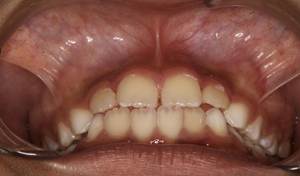

Análisis intraoral: Al observar la boca del paciente nos encontramos que la mucosa está húmeda y lubricada con pigmentación melánica, el frenillo es de inserción mucosa; hay poca inflamación de las encías. El paladar duro es profundo. El paciente está en dentición mixta, existe una mordida cruzada anterior con apiñamiento en el sector anteroinferior. En el arco superior se observa un diastema entre los incisivos centrales superiores permanentes, también se observa que estos dientes están ligeramente rotados. La relación molar de ambos lados es de clase III y la relación de los caninos deciduos también es de clase III.

Fig.3 Fotografía intraoral de frente Fig.

4 Fotografía intraoral de 45°

Fig. 5 Fotografía intraoral lado derecho Fig. 6 Fotografía intraoral lado izquierdo